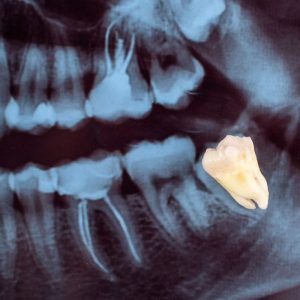

A wisdom tooth extraction removes one or more of the third molars that usually come in during the late teens or early twenties. These teeth often become problematic, causing pain, infection, or crowding and necessitating their removal for good oral hygiene. How I know If my wisdom are coming? For more information about it you can read more here.

You will first get a very comprehensive consultation. Our dental experts use digital X-rays and 3D imaging to assess your wisdom teeth and prepare a custom treatment plan that suits your needs.